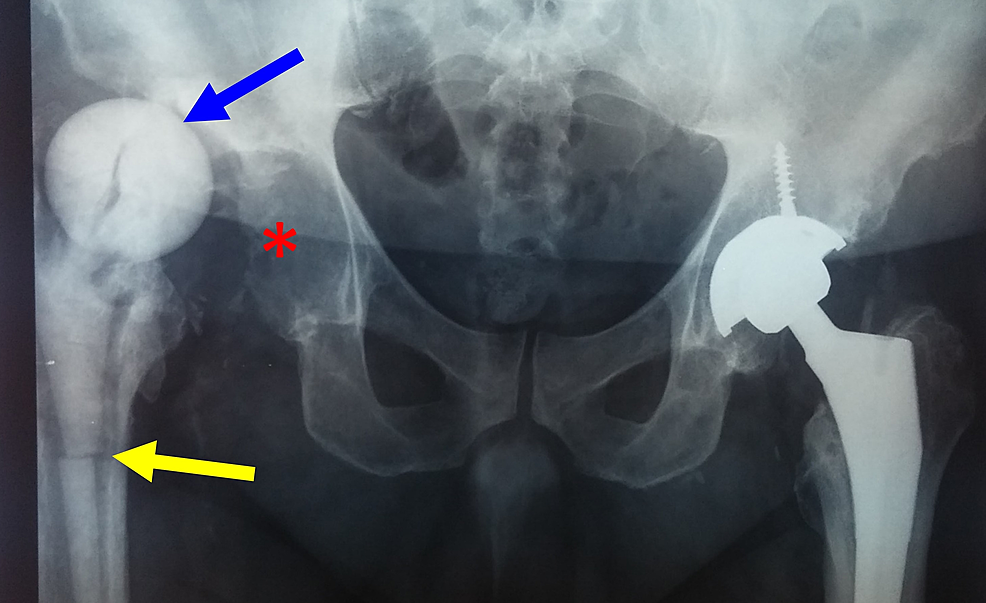

Right hip xray after the insertion of the second antibiotic cement Hip Spacer Complications The use of “functional” spacers may allow patients to return to daily living while optimizing their health for revision surgery. The rehabilitation program following hip spacer implantation emphasizes early, controlled functional range of motion to prevent hip. Temporary spacers used in the staged revision of a hip prosthetic joint infection (pji) have been associated with several mechanical. The aim of. Hip Spacer Complications.